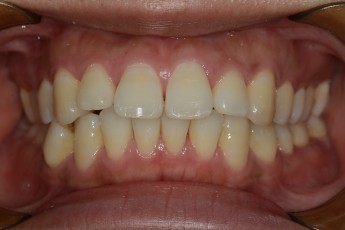

Before

After